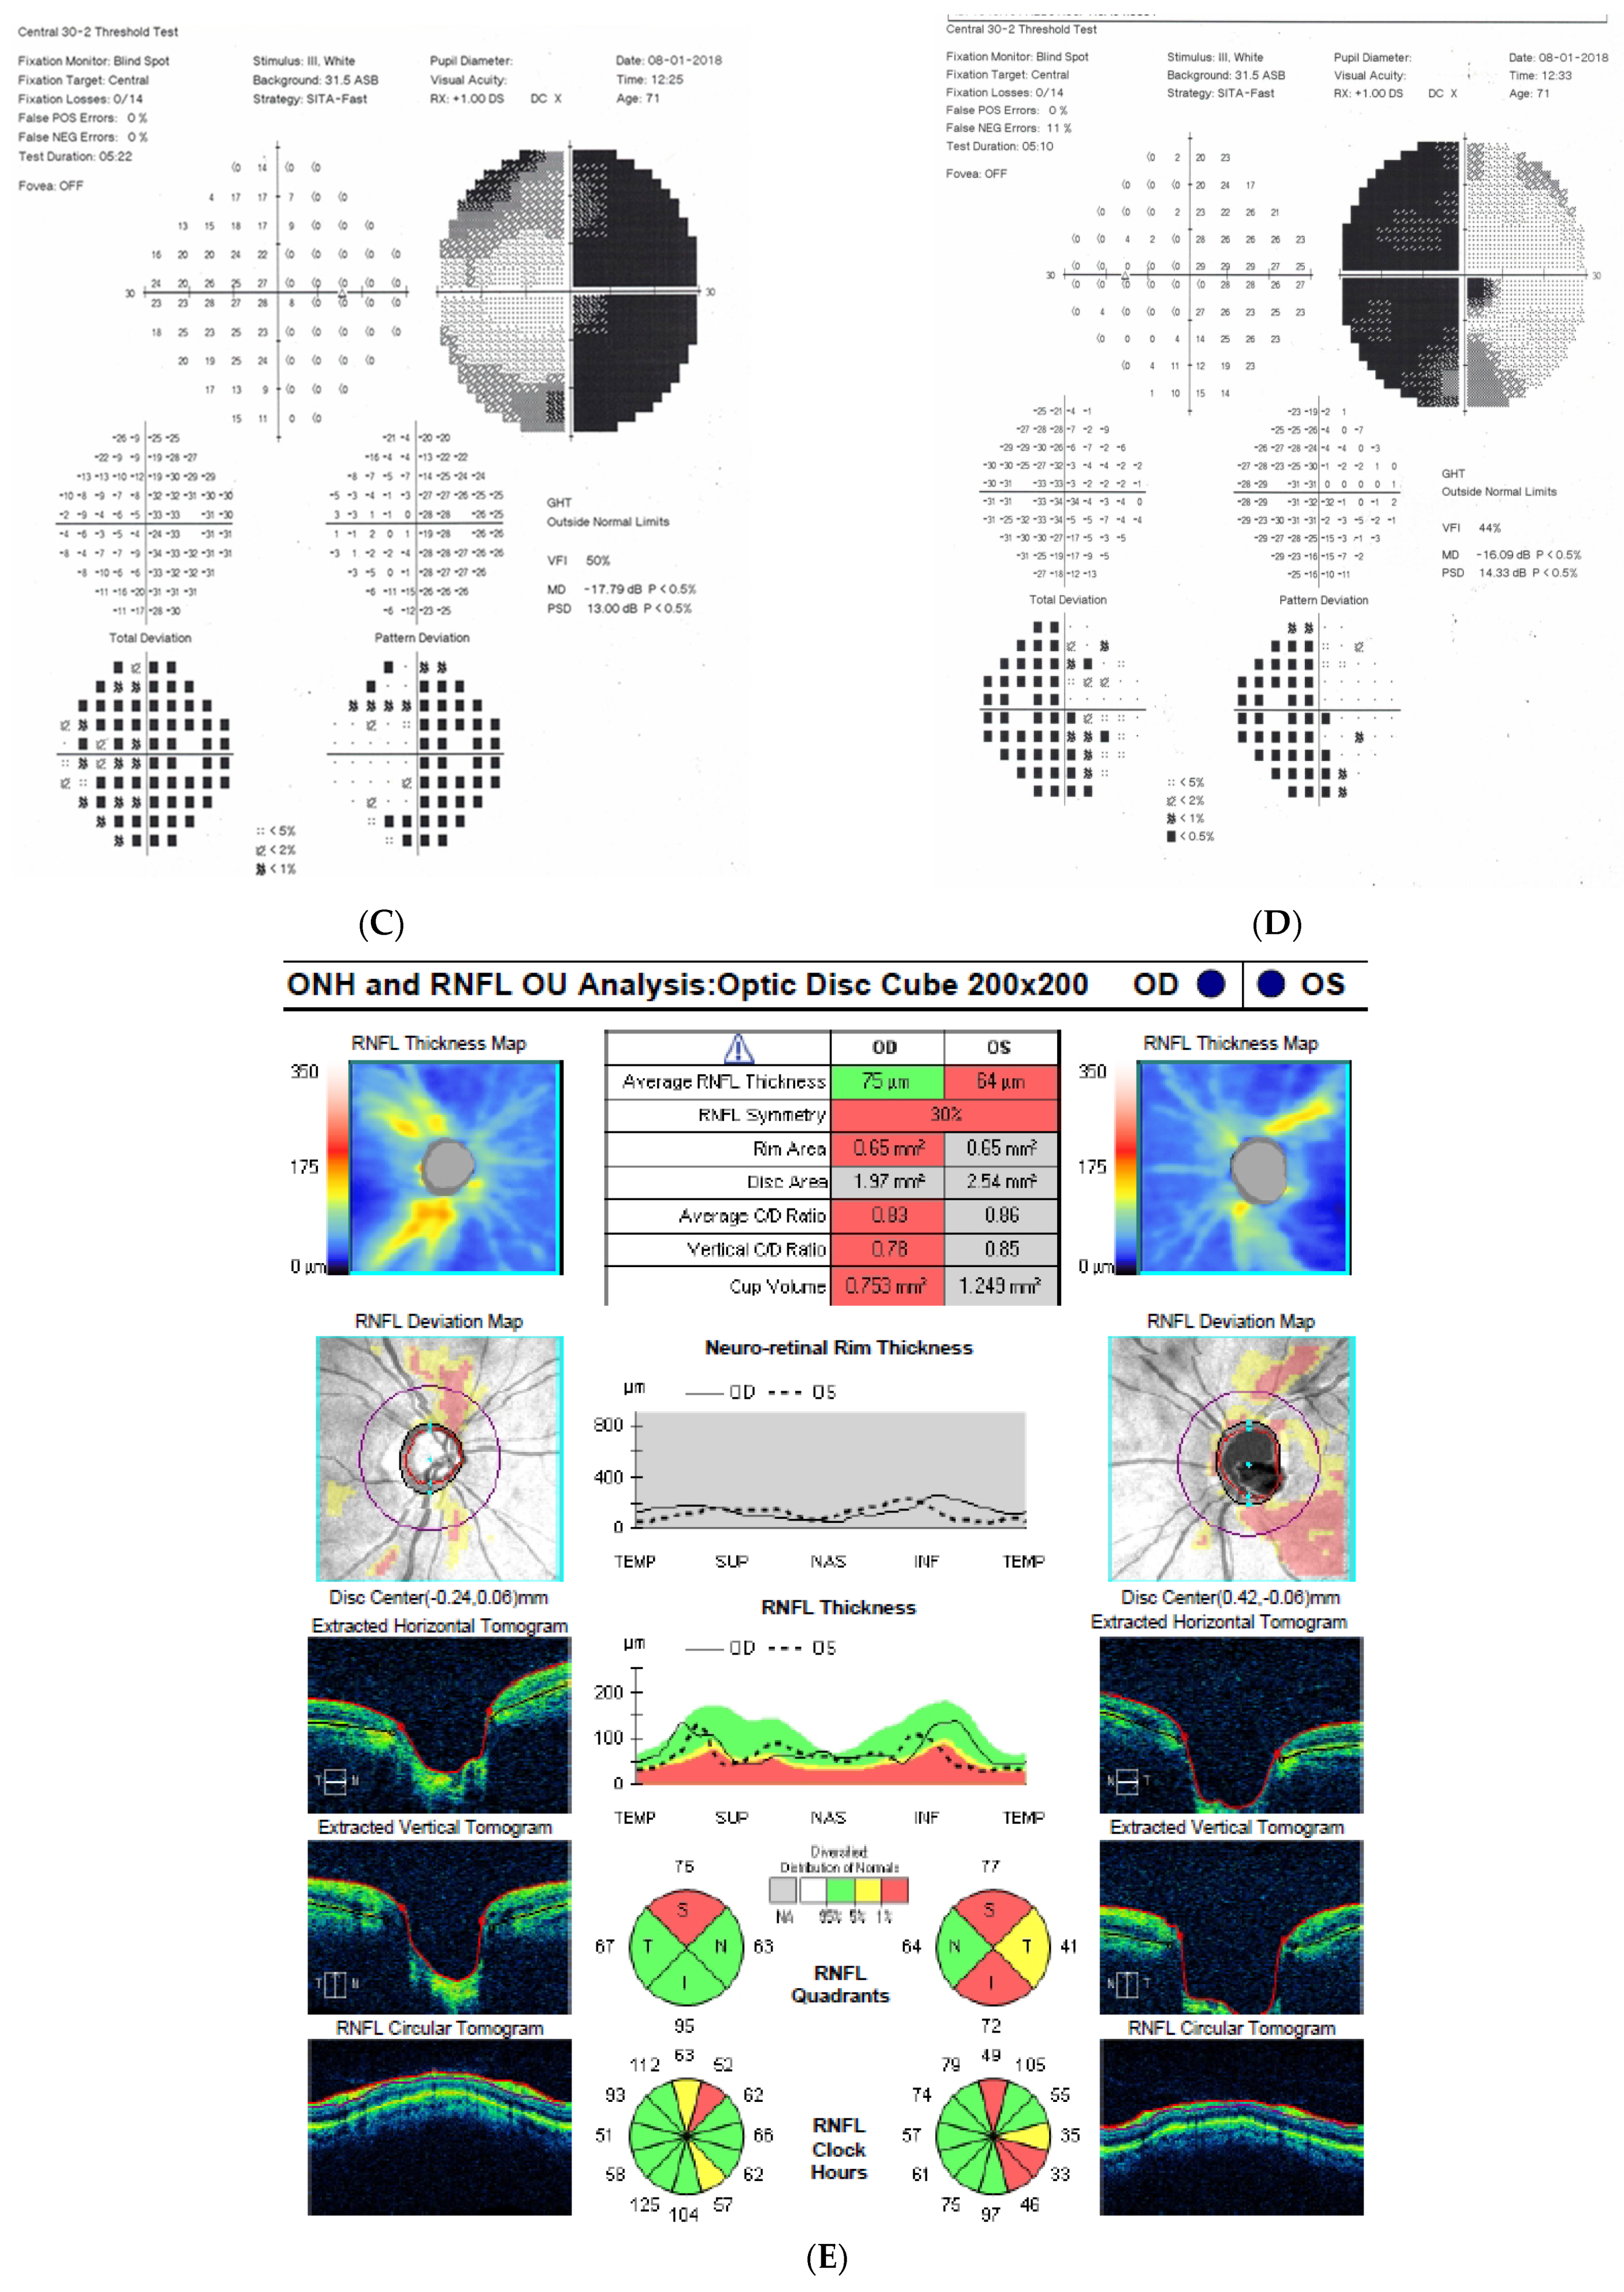

2.2. Case 2

2.3. Case 3

2.4. Case 4

2.5. Case 5